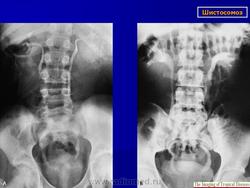

Бильгарциоз (Schistosomiasis) мочевого пузыря